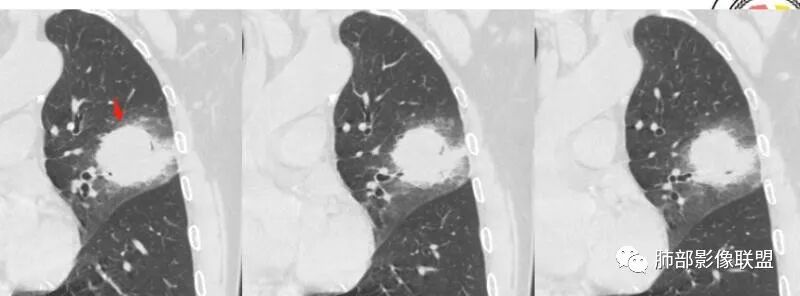

左肺上叶类圆形软组织影,边界较清楚,其内密度均匀,外侧缘可见空气新月征,并可见点状钙化,增强扫描可见均匀强化,病灶周围可见磨玻璃渗出性密度影,斜裂侧光滑平整。考虑炎性病灶,以肉芽肿性炎症为主(如真菌性肉芽肿),鉴别结核(无卫星灶,无多态性),肺癌(无毛刺,分叶等恶性征象,)细菌性炎症(密度一般不这么致密,很少钙化及空气新月征)。

左肺上叶类圆形软组织影,界清,内见空洞影,病灶周围斑片影,可见空气支气管征,未垮叶。考虑炎性病变,糖尿病四大金刚,肺克?毛霉?

老年男性,血糖升高六年,反复咳痰咳嗽3周,左肺上叶近斜裂类圆形肿块影,边缘伴磨玻璃影,边界不清。内部可见支气管走行、钙化、小空洞,叶间裂局部膨隆,增强扫描轻度强化,内部可见小的低密度区,边界尚清。考虑为炎性病变可能性大。

左肺叶裂旁实变影,宽基底与叶裂胸膜相连,边缘平直,部分略膨隆,病灶近段及上段支气管深入病灶内,部分壁略增厚,远端支气管截断,似有小空泡,壁规则,内部可见高密度钙化,周围可见模糊的GGO,血象正常,考虑结核(NTM),鉴别隐球菌,奴卡,放线菌。

老年男性,66,反复咳嗽、咳痰3月。糖尿病,血象不高。

胸部CT:左肺上叶类圆形肿块影,边界较清楚,密度较均匀,内可见小片坏死、偏心空洞、空气新月征、点状钙化,周围晕、絮状渗出、边缘模糊,支气管扩张、充气征、支气管进入病灶堵塞,叶裂牵拉明显,增强扫描中度均匀强化,纵隔可见淋巴结。考虑:炎性病灶,肉芽肿性炎症,曲霉?毛霉?鉴别:TB,淋巴瘤。

左上肺类圆形肿块影,边界较清楚,支气管通畅略扩张,周围磨玻璃影,其内密度均匀,外侧见空气新月征,且见点状钙化。叶间裂光滑稍膨隆。老年男性,糖尿病,高血压,痰培养克雷伯菌。综合考虑炎性病灶,克雷伯合并真菌感染,曲霉。结核合并真菌。鉴别肺癌合并感染。

左肺上叶类圆形软组织影,边界稍模糊,其内密度均匀,外侧缘可见空气新月征,并可见点状钙化,增强扫描渐进性强化,病灶周围可见磨玻璃影,斜裂侧光滑平整,气管未见明显闭塞,淋巴结未见肿大,糖尿病患者,首先考虑感染性变,结核并曲霉?

我标示一下,尖后段搭到一部分,前段也占了一点点。

主体在舌段